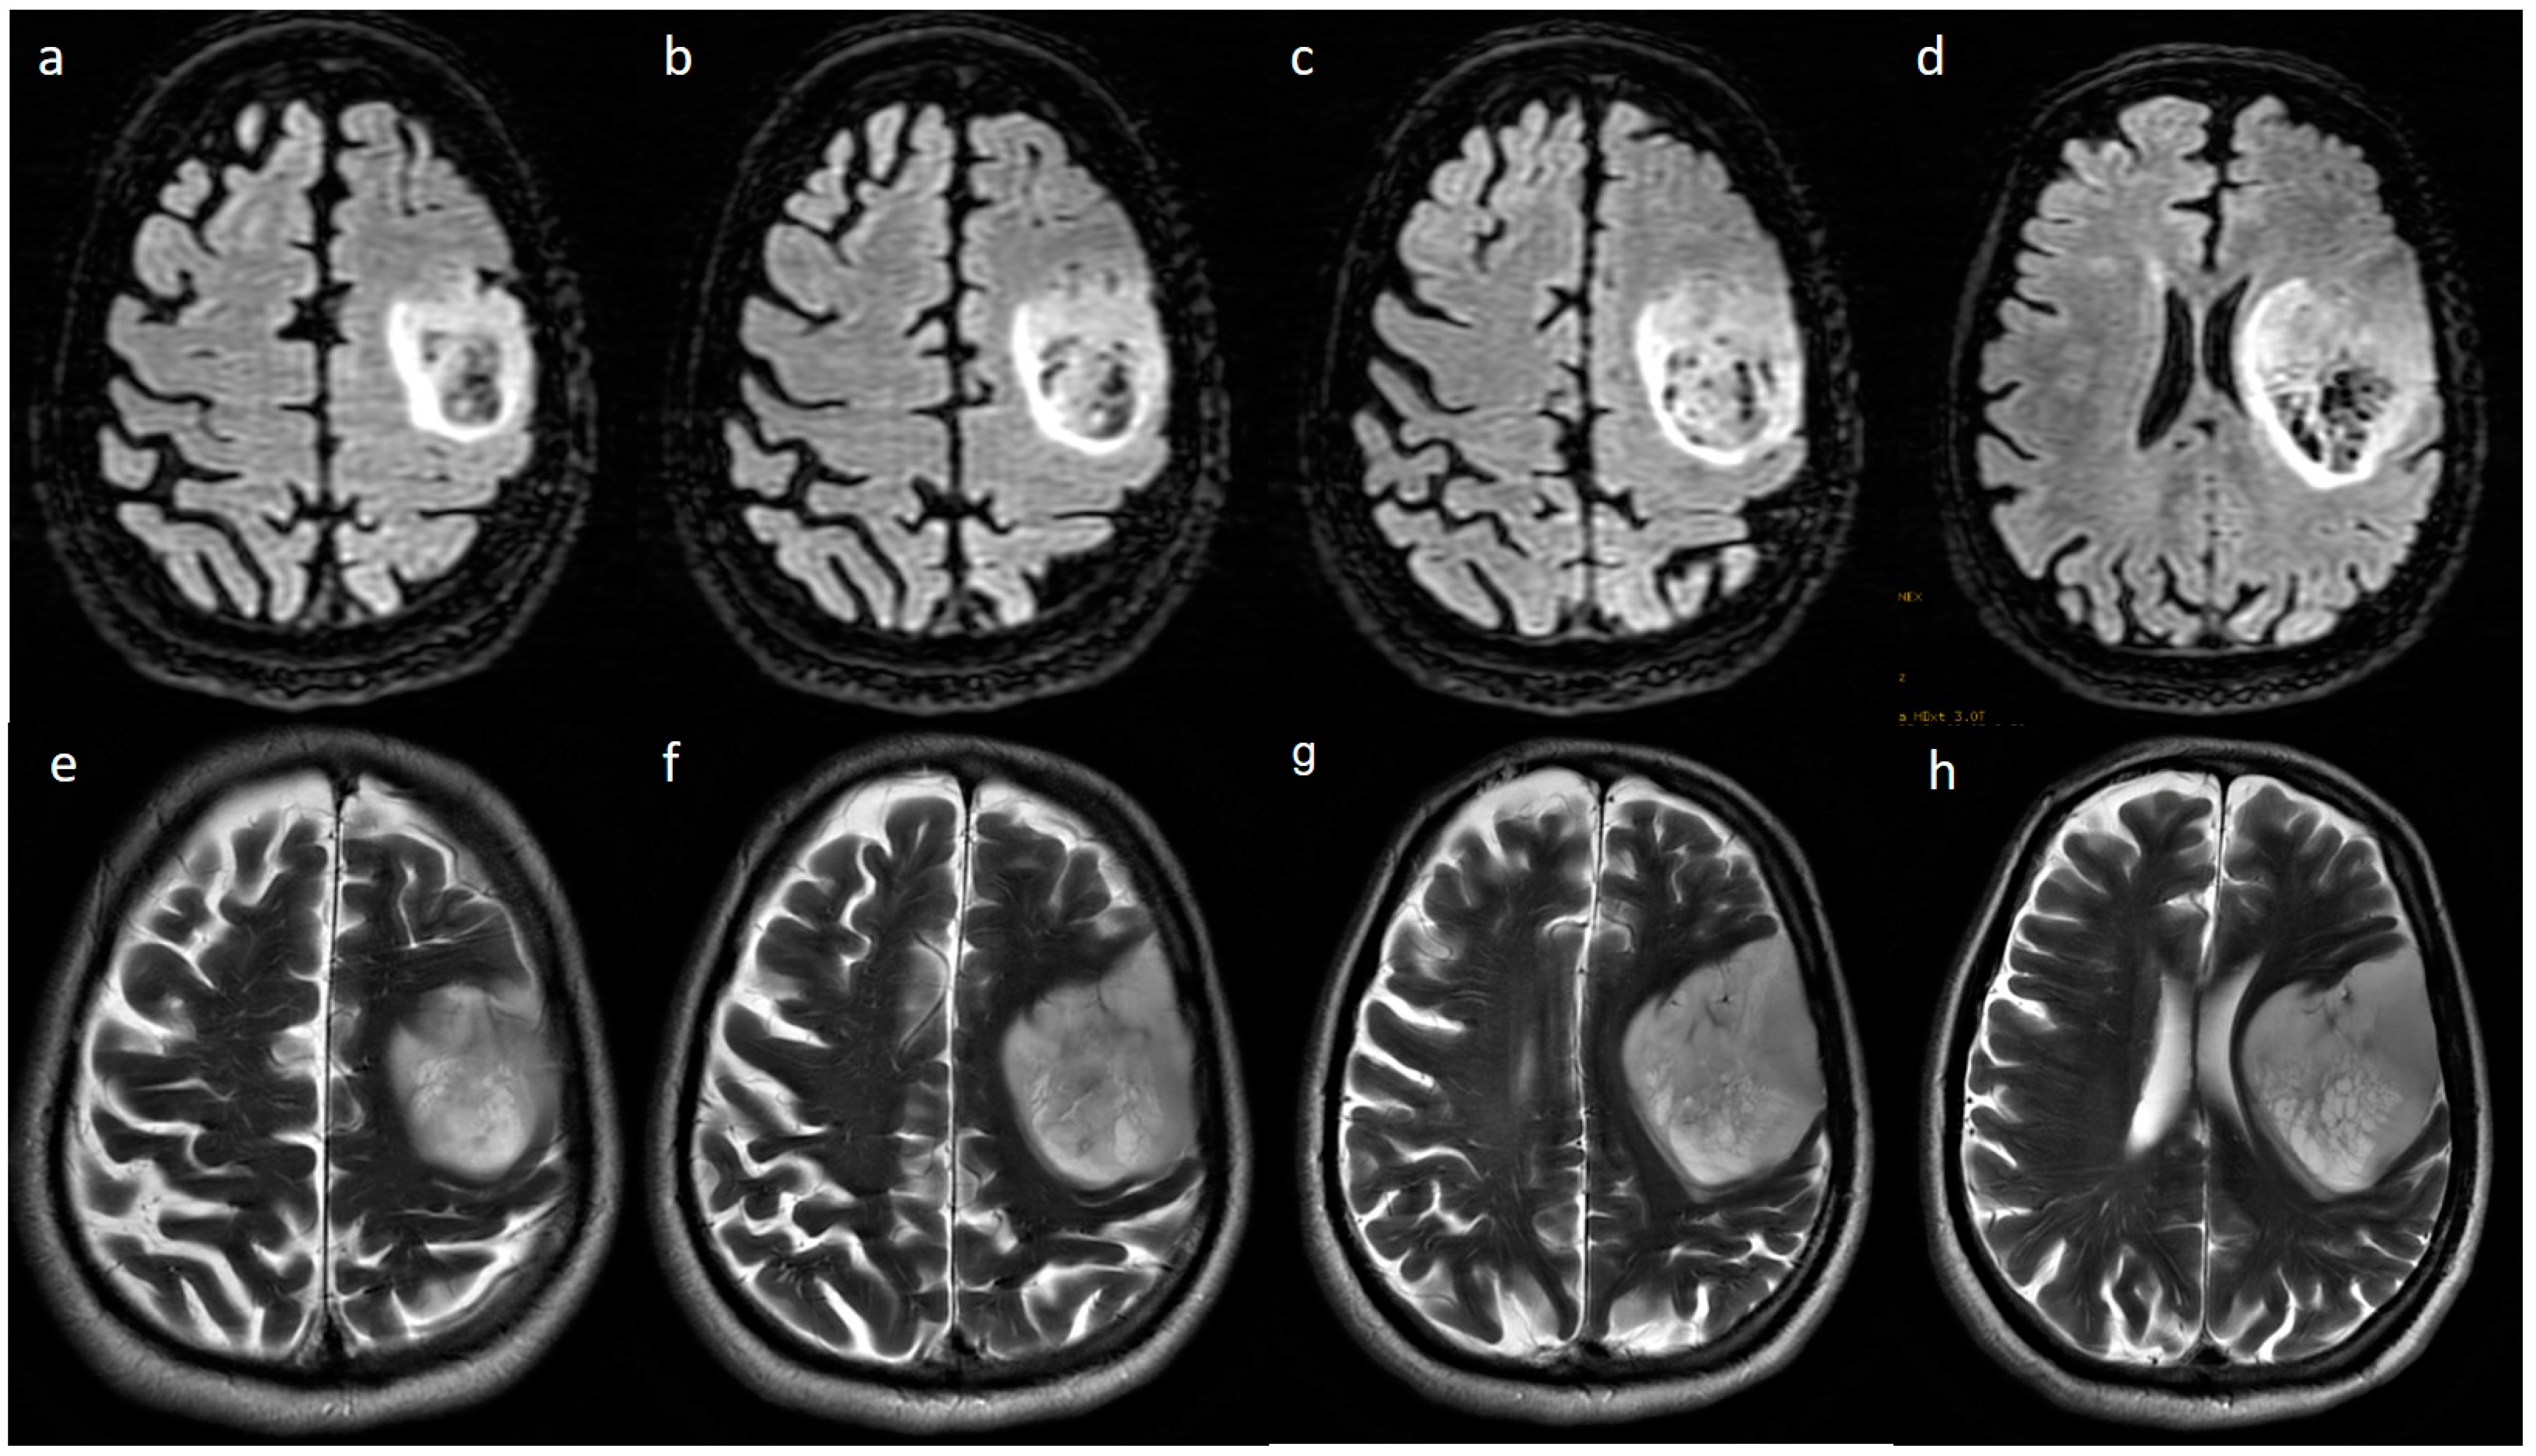

| Variable | Parameter | IDH-Mutated (n = 19) | IDH-Wildtype (n = 129) | p-Value |

|---|---|---|---|---|

| Enhancement I | Mild | 9 (47.4) | 5 (3.9) | <0.001 |

| Moderate | 6 (31.6) | 25 (19.4) | ||

| Severe | 4 (21.1) | 99 (76.7) | ||

| Enhancement III | Rim | 6 (31.6) | 104 (80.6) | <0.001 |

| Nodular | 0 | 2 (1.6) | ||

| Patchy | 11 (57.9) | 13 (10.1) | ||

| Solid | 2 (10.5) | 10 (7.8) | ||

| Necrosis | None | 3 (15.8) | 3 (2.3) | <0.001 |

| <25% | 11 (57.9) | 14 (10.9) | ||

| 25- 50% | 2 (10.5) | 35 (27.1) | ||

| >50% | 3 (15.8) | 77 (59.7) | ||

| Dural enhancement | AbsentPresent | 07 (70.0) | 31 (24.0)48 (52.7) | 0.013 |

| Edema | None | 3 (15.8) | 3 (2.3) | 0.025 |

| <tumor volume | 11 (57.9) | 68 (52.7) | ||

| Equal to tumor volume | 4 (21.1) | 35 (27.1) | ||

| >tumor volume | 1 (5.3) | 23 (17.8) | ||

| Cysts * | No | 11 (57.9) | 115 (89.1) | 0.001 |

| Yes | 6 (31.6) | 14 (10.9) | ||

| Subcortical involvement | Involved | 18 (94.7) | 94 (72.9) | 0.044 |

| Not involved | 1 (5.3) | 35 (27.1) | ||

| rCBV | Median (IQR) | 1.8 [1.4–2.0] | 2.6 [1.9–3.5] | 0.001 |